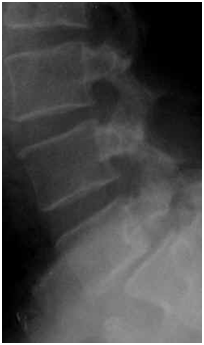

При сравнении рентгенограмм в динамике может быть выявлено увеличение степени спондилолистеза (Рис. №3).

Рис. №3. Рентгенограммы больного Н. А – 2009 год, Б - 2013 год.

1.Обзорная рентгенография.

Рис. №4. Рентгенологическая картина спондилолистеза.

2.Рентгенография с функциональными пробами

Данный метод исследования применяется с целью определения функционального состояния позвоночных сегментов, определения формы спондилолистеза (стабильная, нестабильная). Функциональные рентгенограммы выполняют в боковой проекции в положении максимально возможного сгибания и разгибания (Рис. № 5).

Рис. №5. Определение нестабильности позвоночного сегмента. функциональные рентгенограммы (нестабильность в сегменте L4-5): А – сгибание; Б – разгибание.